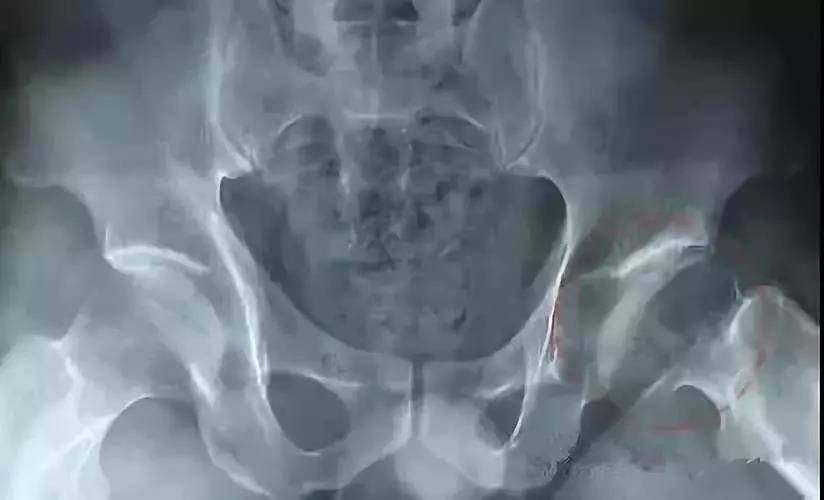

(1)股骨头坏死的 X 线表现

初期

髋关节间隙轻度增宽,以关节中下为主,主要因关节软骨增宽,股骨头外移所致,早期股骨头在外移2mm以内,晚期可达5mm,一般认为是关节旁及关节内软组织充血所致,可以逆转。

中期

股骨头皮质可以断裂形(台阶状)成角,基底处出现平行的双皮质征(双边征),其中台阶征及双边征是X线判断股骨头塌陷的早期征象,随后股骨头广泛脱位和碎解,其内可见死骨、裂隙、硬化和透光区,股骨头压缩变扁平,轮廓不规则,关节腔最初因股骨头变扁而增宽。股骨颈下方出现皮质增厚或骨膜增生,关节间隙可呈不规则变窄,髋臼关节面增生硬化,Sheaton线不连续,股骨头碎块可成为关节游离体。